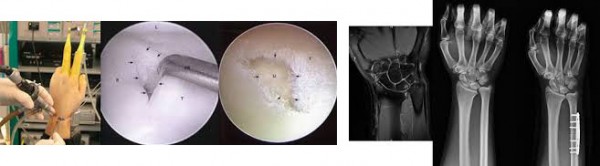

수술적 치료법

관절내시경을 통해 파열 부위를 다듬거나 부위에 따라 봉합술을 시행하게됩니다. 손목뼈 간의 충돌로 인한 관절연골 손상이 발견된 경우에는 연골 성형술과 더불어 길어진 척골을 단축시키는 수술을 함께 시행하게 됩니다. 수술 후 약 10일 정도 부목 고정을 실시하게 되는데 다른 수술에 비해 일상생활로의 복귀가 빠른 것이 특징입니다. 하지만 동반 손상이 있을 경우에는 부목

고정 기간이 길어질 수도 있습니다.